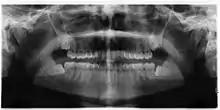

Wisdom teeth likely become impacted because of a mismatch between the size of the teeth and the size of the jaw. Impacted wisdom teeth are classified by their direction of impaction, their depth compared to the biting surface of adjacent teeth and the amount of the tooth's crown that extends through gum tissue or bone. Impacted wisdom teeth can also be classified by the presence or absence of symptoms and disease. Screening for the presence of wisdom teeth often begins in late adolescence when a partially developed tooth may become impacted. Screening commonly includes clinical examination as well as x-rays such as panoramic radiographs.

If the tooth cannot be assessed with clinical exam alone, the diagnosis is made using either a panoramic radiograph or cone-beam CT. Where unerupted wisdom teeth still have eruption potential several predictors are used to determine the chance of the teeth becoming impacted. The ratio of space between the tooth crown length and the amount of space available, the angle of the teeth compared to the other teeth are the two most commonly used predictors, with the space ratio being the most accurate. Despite the capacity for movement into early adulthood, the likelihood that the tooth will become impacted can be predicted when the ratio of space available to the length of the crown of the tooth is under 1.[5]:141

Screening

There is no standard to screen for wisdom teeth. It has been suggested, absent evidence to support routinely retaining or removing wisdom teeth, that evaluation with panoramic radiograph, starting between the ages of 16 and 25 be completed every 3 years. Once there is the possibility of the teeth developing disease, then a discussion about the operative risks versus long-term risk of retention with an oral and maxillofacial surgeon or other clinician trained to evaluate wisdom teeth is recommended. These recommendations are based on expert opinion level evidence.[19] Screening at a younger age may be required if the second molars (the "12-year molars") fail to erupt as ectopic positioning of the wisdom teeth can prevent their eruption. Radiographs can be avoided if the majority of the tooth is visible in the mouth.